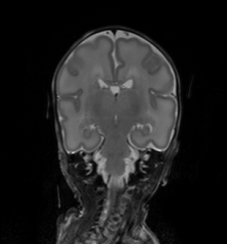

The performance for the images acquired at 30 weeks PMA was evaluated on the independent set of 5 images not included in the parameter estimation, using the other 5 images as training data. For the other image sets, the method was retrained using representative training data. Because of the limited number of available training images, the performance on the coronal and axial images acquired at 40 weeks PMA was evaluated in leave-one-subject-out cross-validation for each set. The average Dice coefficients and mean surface distances for each tissue class are shown per set in Table II: Experiments 1, 3, and 4. The segmentation results in one slice of one image of each of the test sets are shown in Figure 4.

Given that a larger set of manually annotated images of ageing adults was available, their performance was evaluated using 5 images as training data and 15 images to test the performance (Table II: Experiment 6, and Figure 4). This furthermore allowed (indirect) comparison with the results of the MRBrainS13 challenge, which is performed using the same training and test images, except that only 3 combined tissue classes, namely WM, GM, and CSF are evaluated in the challenge.

Similar to the images of ageing adults, the images of young adults were evaluated using 5 images as training data and 10 images to test the performance (Table II: Experiment 7, and Figure 4). Additionally, the performance on the independent test set of 20 images [44] is evaluated using all 15 images as training data (Table II: Experiment 8).

The method achieved accurate segmentations in terms of Dice coefficients for all tissue classes except mWM in the neonatal images. mWM consists, especially in the images acquired at 30 weeks PMA, of very few voxels, hence each mislabelled voxel strongly influences the Dice coefficient. Furthermore, this tissue is poorly visible in T2-weighted images and slightly better visible in T1-weighted images, which makes the manual annotation very difficult and prone to inter-observer variability [35]. This consequently has influence on the performance of the neighbouring tissue classes, which can be seen from e.g. the performance on BS for the coronal images acquired at 40 weeks PMA (Table II: Experiment 3). Even though the performance in terms of Dice coefficients is lowest for mWM, the location of the tissue class is quite well recognised by the method, even based on T2-weighted images only. This can be seen from the mean surface distances (Table II) and from Figure 4: e.g. for the coronal images acquired at 40 weeks PMA, where mWM is recognised but does not follow the exact shape of the manual segmentation.